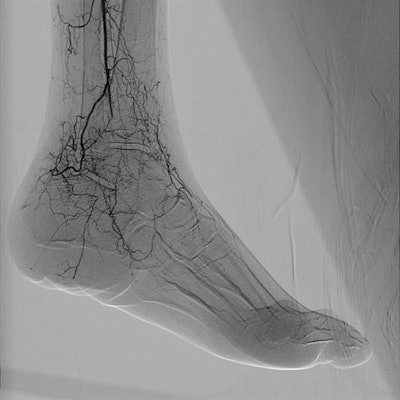

Alphenix is an interventional angiography platform that Canon Medical Systems is highlighting at the congress in Vienna. Enhancements include a conebeam CT mode called AlphaCT for low-contrast imaging and a real-time autopixel shift mode that cleans up imaging in less than 10 msec. The platform also includes the Hi-Def Detector, a flat-panel digital detector available on the Alphenix Biplane and Alphenix Core + systems.